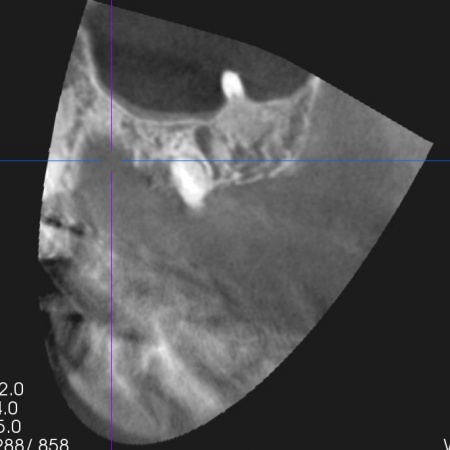

患者様は、人工歯根であるインプラントによる治療を希望されていましたが、レントゲン撮影の結果では、インプラントを入れるために必要な骨の量が足りていません。

また、患者様は骨粗鬆症の治療を受けている最中で、骨粗鬆症の薬を服用している場合、骨密度が低いことでインプラントがしっかりと顎の骨に固定されなかったり、顎の骨が壊死したりするリスクがあります。

続いて、不足している骨を補強しつつ、インプラントを埋入した土台を安定させるための骨補填を行いました。

3ヶ月後、顎の骨の状態が良好であることを確認し、インプラントを埋入する手術を実施しました。